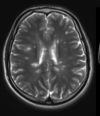

identify

multiple sclerosis

plaque (lesion) perpendicular from lateral ventricle

identify

multiple sclerosis

plaque (lesions) perpendicular from lateral ventricles